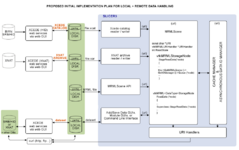

visualiztionRemote Data Handling allows uploads and downloads from image informatics frameworks such as BIRN, and XNAT

OpenIGTLink interfaces to devices such as scanners, trackers, and robots